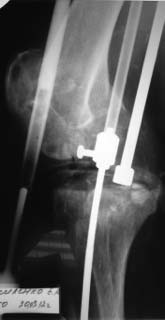

Уважаемые коллеги! Пациент мужчина 62 года эндопротезирование коленного сустава в

сентябре 2011 в одном из соседних учреждений. Множественные операции по восстановлению

связок в анамнезе

Под наше наблюдение попал спустя 3 месяца с клиникой глубокой перипротоезной инфекции.

Гнойный свищ, MRSA в посеве. Выполнено удаление протеза, некрэктомия, установка

цементного спейсера. Заживление первичное, а\б терапия по посевам, в течении 2 месяцев

положительная динамика, нормализация лабораторных показателей. В последующем усиление

болей, отек, разрушение спейсера по рентегнограммам. Взят в операционную для повторной

некрэктомии, удаления спейсера. Во время операции выявлено- отсутствие явного гнойного

содержимого, ткани более жизнеспособные чем во время первого удаления, отсутствие

значительного прогрессирования костных дефектов. Решено от одномоментного артродеза

воздержаться, конечность стабилтзирована дистракционным аппаратом. В

интраоперациооных посевах St.aureus В настоящее время две недели после операции, встает

вопрос о возможностях далнейшего лечения. Ревизонное колено? Еще раз после спейсера или

сразу? Или артродез